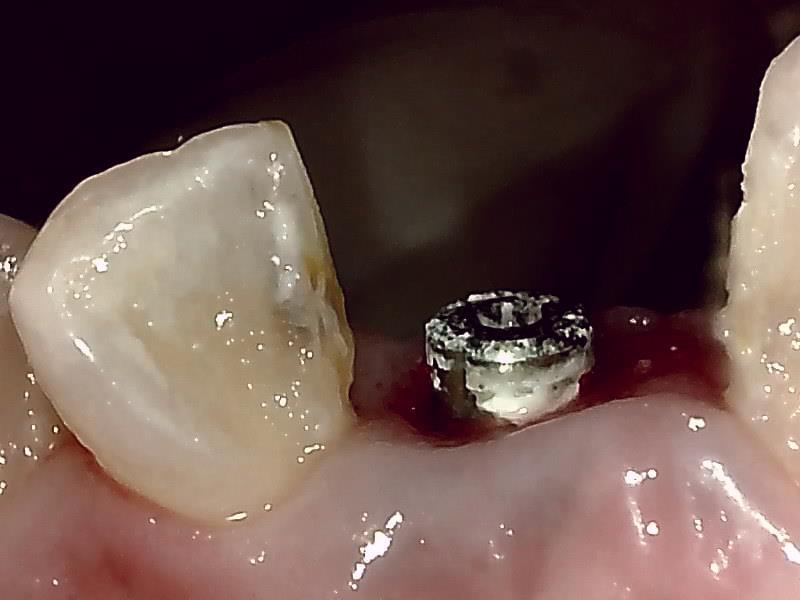

抜糸後、2週間経過した歯肉の状態です。

歯肉の整形 とても綺麗な良い歯肉の状態です。

アバットメント装着